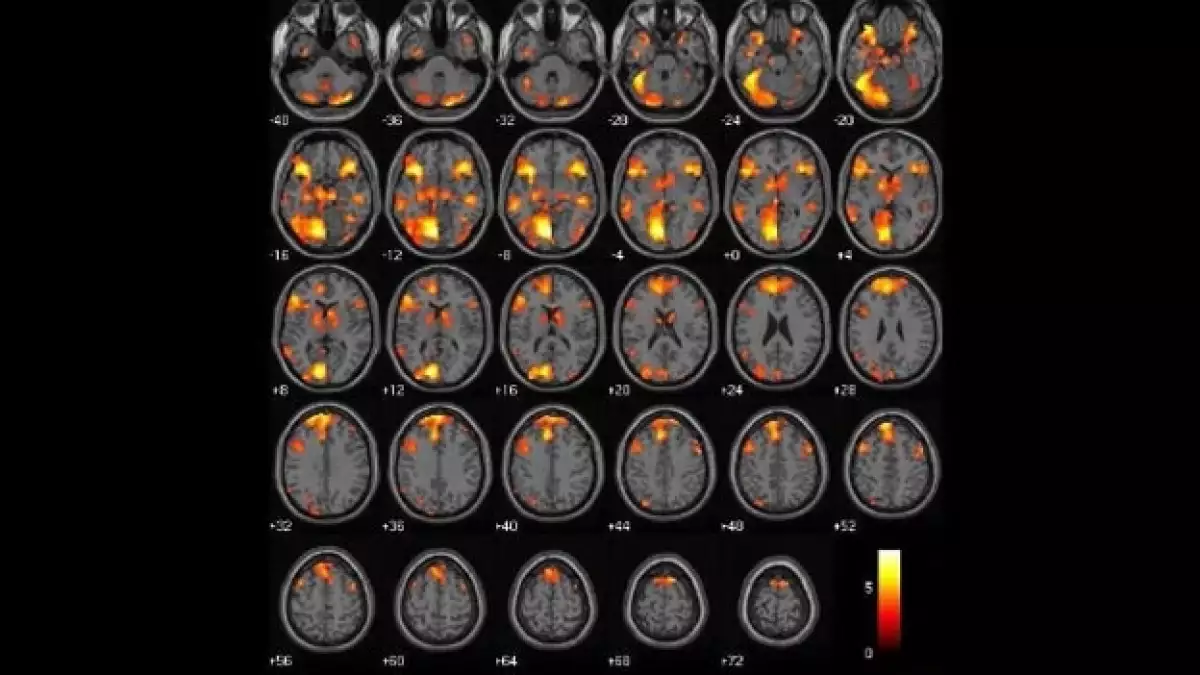

Los investigadores interesados en la neurociencia de la moralidad investigan qué redes del cerebro están involucradas en esas decisiones, y qué podría representar para las diferencias individuales de las personas en los juicios. Los estudios sobre el tema a menudo involucran pequeñas muestras de personas; la resonancia magnética funcional gasta mucho tiempo y dinero, pero los patrones surgen a medida que más resultados entran.

Los científicos mostraron que hay una red específica de regiones en el cerebro involucradas en mediar el juicio moral. Un estudio influyente en este tema fue publicado en 2001 y liderado por Joshua D. Greene , profesor en la Universidad Harvard, autor de Moral Tribes: Emotion, Reason, and the Gap Between Us and Them (Tribus morales: Emoción, razón y la brecha entre nosotros y ellos).

En el estudio de Greene se sugirió que tres estructuras cerebrales; la corteza prefrontal media, el cíngulo posterior y el giro angular en los lados derecho e izquierdo, “juegan un papel central en los procesos emocionales que influyen la toma de decisiones personal moral”, escribieron Raine y Yang.

Desde entonces, en otros estudios se confirmó que estas áreas son importantes para procesar la información de las decisiones morales, así como un área llamada la corteza ventral prefrontal.

Varios investigadores sugirieron adicionalmente que las áreas cerebrales involucradas en el juicio moral se superponen con lo que se llama “red modo automático”, que está involucrada en nuestro estado “base” de estar despierto pero descansando. La red también está activa durante “tareas internamente enfocadas incluida la recuperación de memoria autobiográfica, imaginar el futuro, y concebir las perspectivas de otros”, escribieron Randy Buckner y sus colegas en un estudio de 2008 .

Los investigadores utilizaron imágenes de resonancia magnética funcional en 22 hombres psicópatas criminales y 22 hombres saludables que no eran criminales. Encontraron que la mayoría de los participantes dio respuestas similares a dilemas morales utilizados en el estudio, ya sean psicópatas o no.

Pero sus cerebros contaban una historia diferente: los psicópatas tendían a mostrar menos activación en las cortezas medial frontal y cingulada posterior en respuesta a los dilemas morales. Los investigadores también encontraron diferencias en los cerebros de los psicópatas en un análisis de conectividad funcional; quiere decir que, encontraron deterioro en las conexiones entre algunas regiones involucradas en la moralidad y otras áreas.